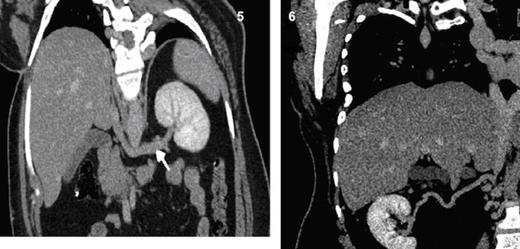

Dilated and tortuous azygous & hemiazygous veins (Fig. 2), with multiple prevertebral and paravertebral collaterals (Fig. 3) as well as superificial collateral veins in the abdominal wall (Fig. 4) were seen. Left renal vein is draining into the hypoplastic segment of IVC (Fig. 5).

Coronal MPR CT image shows a long left renal vein seen draining into the intra-hepatic segment of IVC. Fig. 6 Coronal MPR CT image shows a right renal collateral vessel draining into hypoplastic segment of IVC.